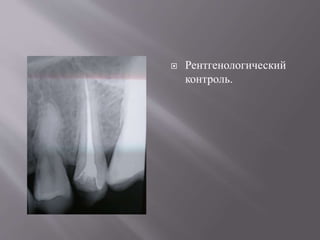

 Рентгенологический

контроль.